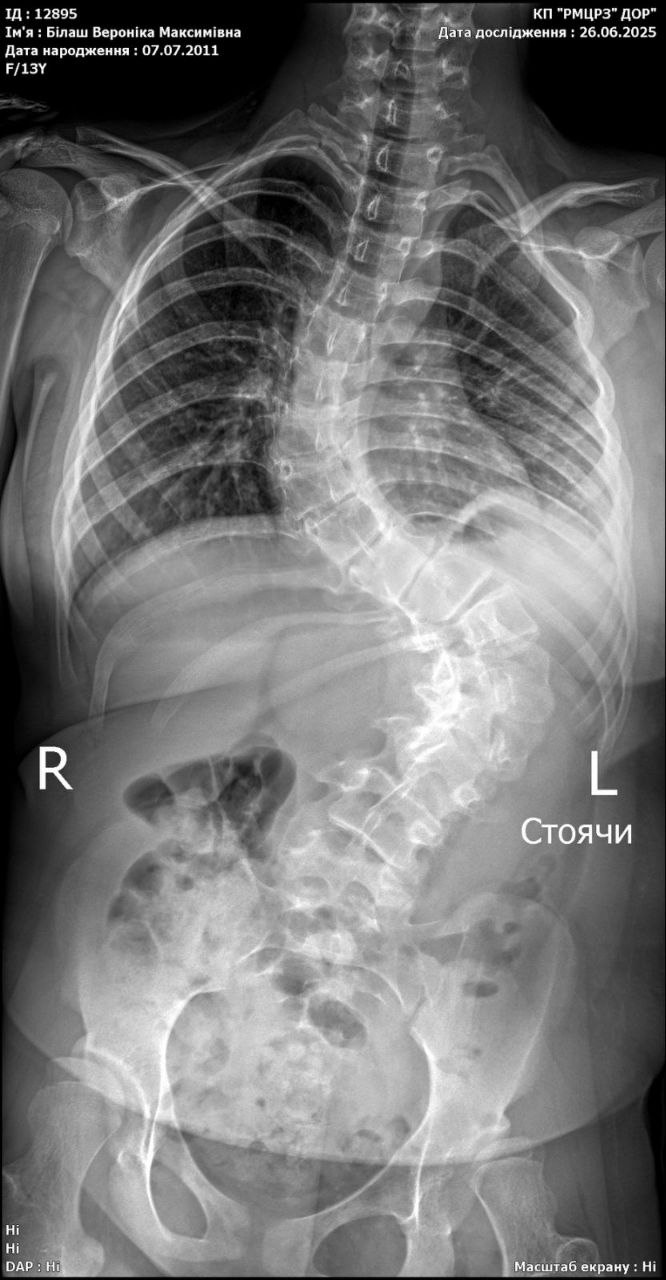

Приблизно 5 років тому нашій доньці був поставлений ще один діагноз - сколіоз 2 ступеню. Згідно з призначенням лікаря, Вероніка носила корсет Шено та відвідувала регулярні заняття з ЛФК. Але нажаль, хвороба прогресувала. На теперішній час їй діагностували 4 ступінь сколіозу, яку можливо лікувати тільки операційним втручанням.

Завідуючий відділення ортопедії та травматології Центру матері та дитини імені Руднєва Дмитро Петренко (м. Дніпро): «У Вероніки диспластичний грудо-поперековий сколіоз 4-го ступеня. За останній час стан дівчинки погіршився, деформація хребта прогресує, посилився біль в грудях і спині, наростає задишка. З плином часу буде прогресувати серцево-легенева недостатність. Потрібно невідкладно провести дівчинці хірургічне лікування з використанням металевої конструкції-імплантату. Даний метод є найбільш підходящим для виправлення сколіозу. Після періоду реабілітації та адаптації Вероніка зможе жити повним життям, забувши про свою недугу».